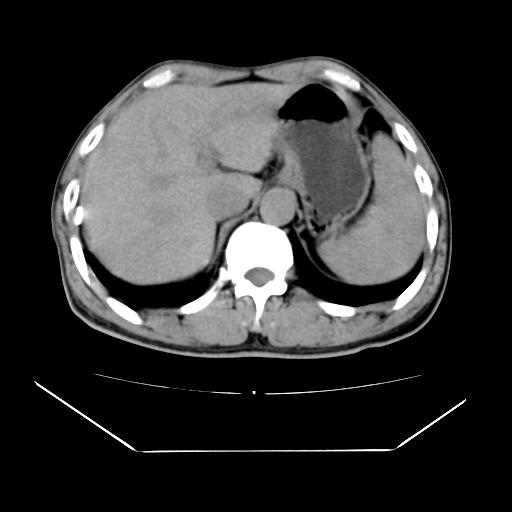

男性,55岁,外院体检afp明显升高,但b超未发现异常,否认乙肝病史。来我院ct增强。有延时扫描。

肝脏右叶动脉期可见低密度影,至延迟期被充填,考虑血管瘤可能性大。

肝右叶病灶

不排除肝右叶肝癌可能。

如果这个是癌灶的话则下腔静脉有瘤栓可能

肝6段血管瘤

血管瘤可能性大。

考虑肝右静脉影。